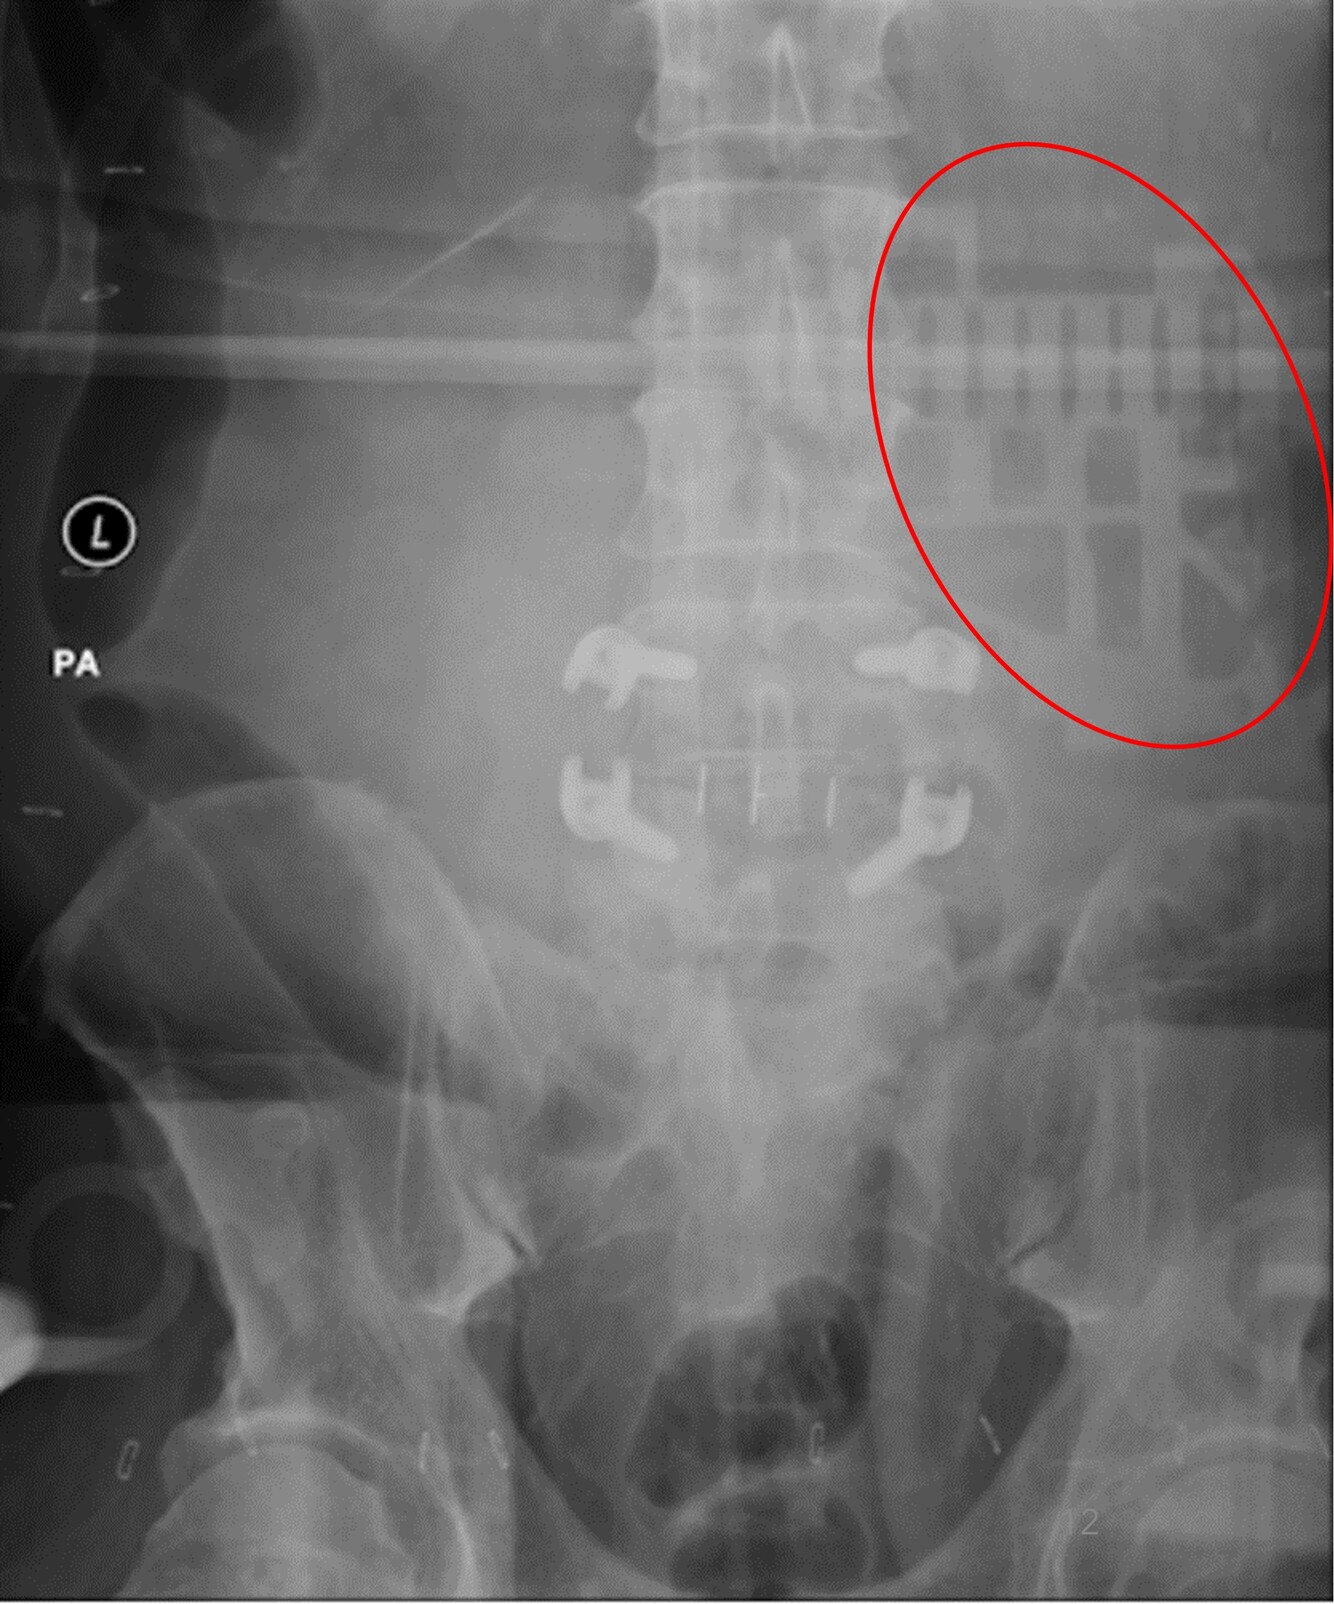

What is the cause of the artifact (red circle) seen

in the attached image?

A

Back scatter from high technique and reduced shielding on back of detector